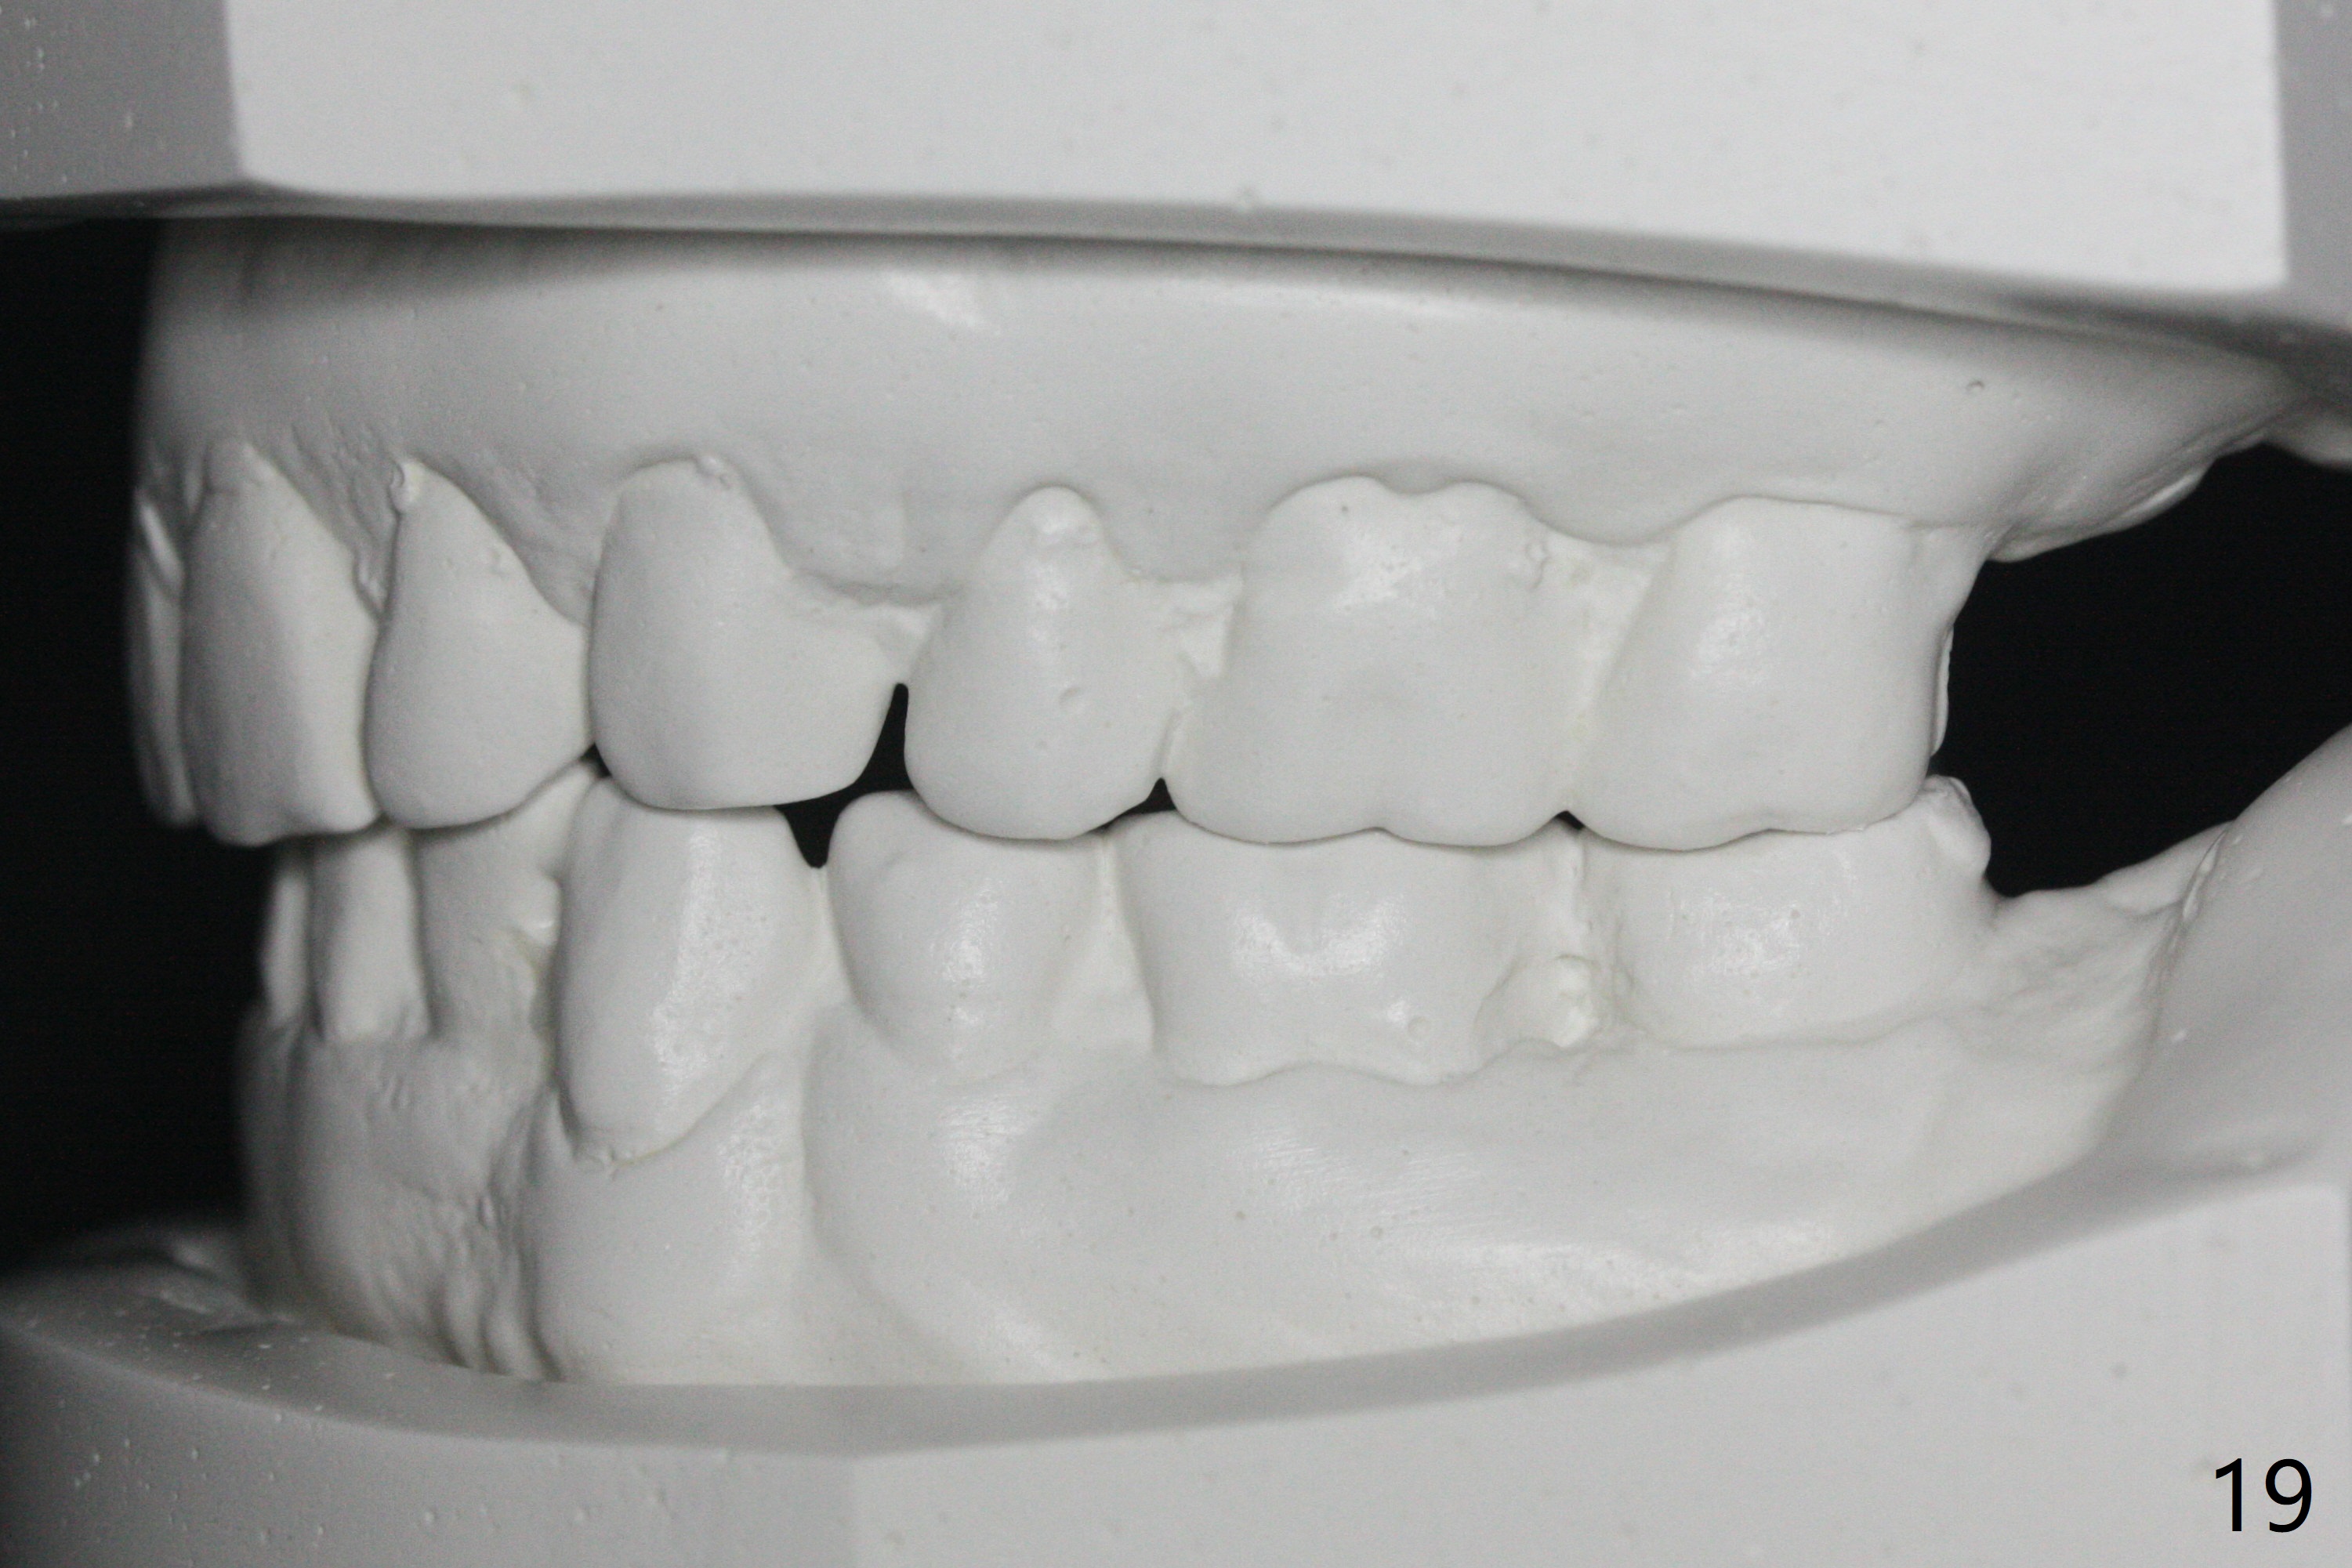

Enough Space For Crowding After Extraction? A 47-year-old man requests orthodontic treatment following SRP in other office (Fig.1-11). For severe crowding and midline shifting, extraction of four of the 1st bicuspids is imminent. Is it enough? To answer the question, model surgery is performed (Fig.12-16). 1st visit: periodontal maintenance, orthodontic consent (emphasizing oral hygiene) extract 4s and possibly L8s and separators. The beauty of this vist is that after local anesthesia and extraction including L8s, it is painless and easy to remove calculus from the proximal surfaces of the neighboring teeth. It is much easier to place separators after extraction. It is expected that there is no gingival erythema when the patient returns for bracketing. Take photos of UR3, similar to Fig.3. Molar banding is also anticipated to be easy with separator placement after extraction. Return to Ortho Cases Xin Wei, DDS, PhD, MS 1st edition 11/23/2017, last revision 04/28/2019